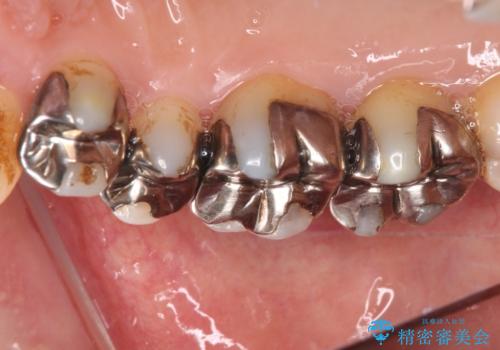

- 奥歯の銀歯をセラミックの白い歯にして、しみる症状も改善したいとのことで来院された患者様です。

知覚過敏の症状が強い歯と、銀歯の範囲や銀歯の下のむし歯が大きい歯は、インレー修復では対応が難しいためオールセラミッククラウンで、インレー修復で対応が可能な歯ではセラミックインレーにて修復することとしました。